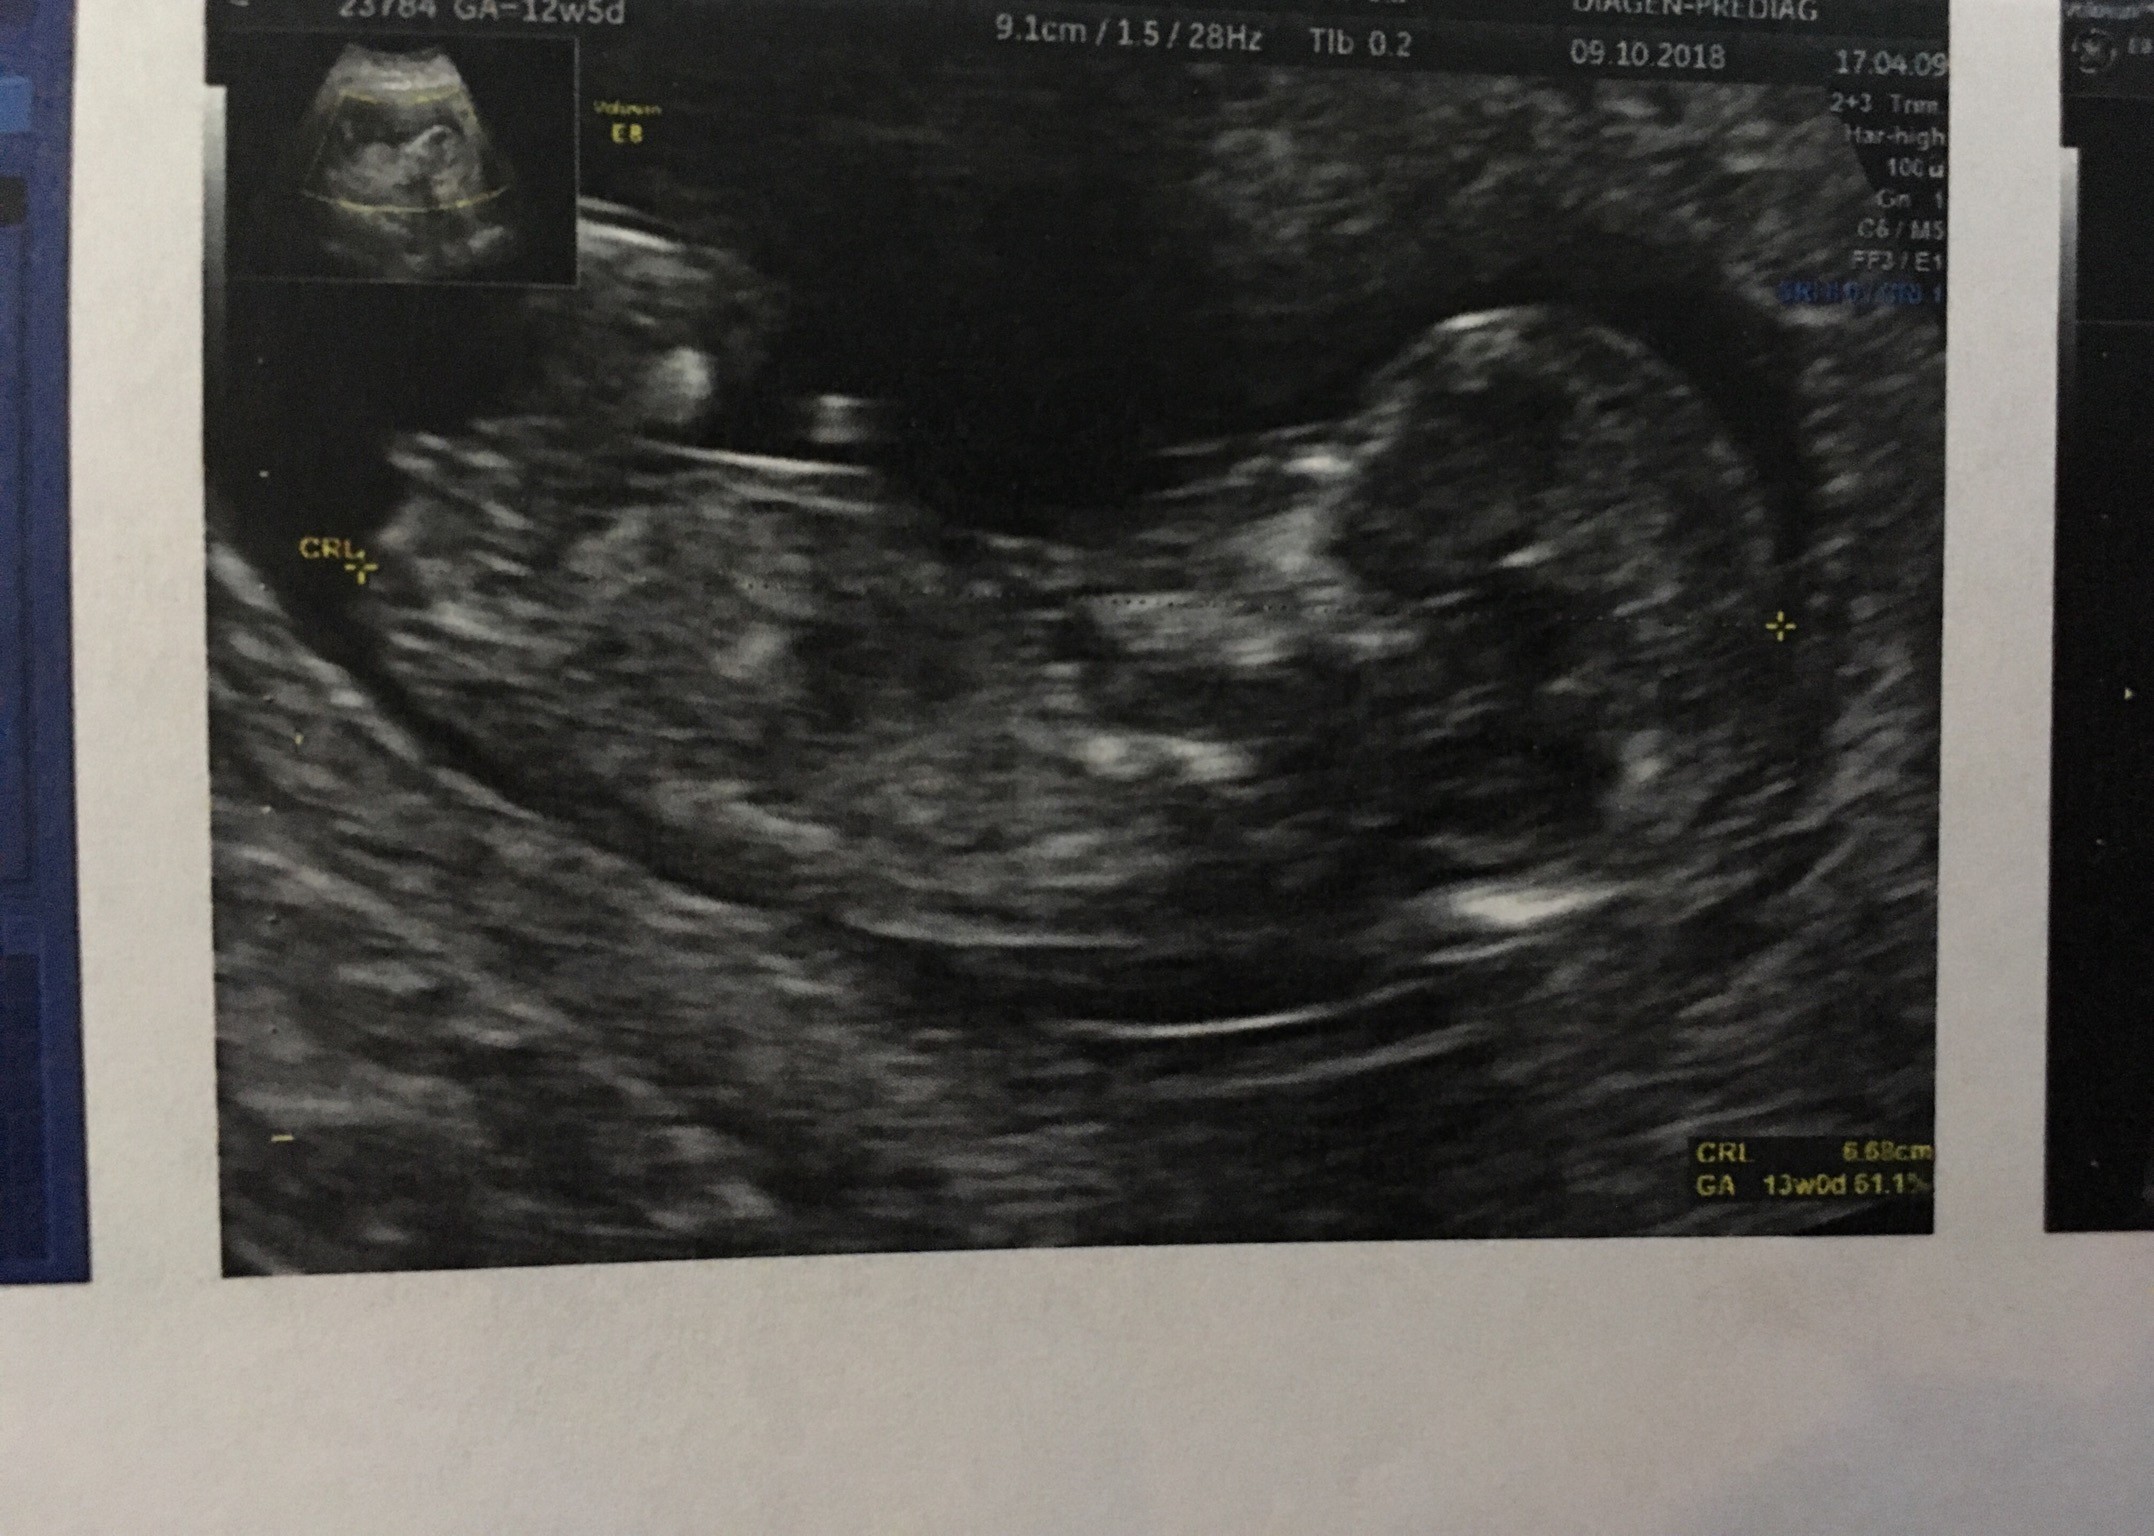

Witam w 19 tygodniu ciąży dowiedziałam się ze będę miała dziewczynkę w 20 tyg okazało się jednak , że to chłopak. Sama już nie wiem bo na jednym usg widać na pewno dziewuche a na drugim chłopca. Może to pempowina ?? Może ktoś mi pomoże rozwiązać ta zagadkę